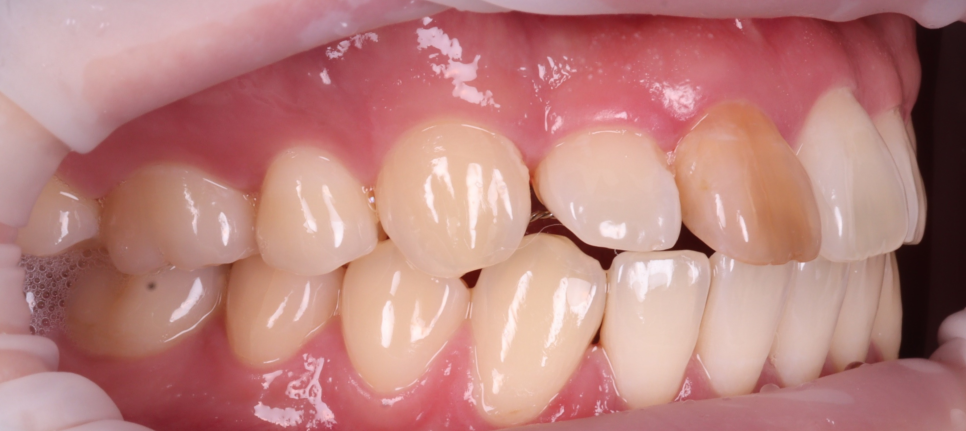

실활치 미백 전, 후 / 촬영일 : 250905 / 250926

최대한 밝게 만들어 놓은 상태에서

더이상 치아가 반응하지 않아

레진 비니어링(페이싱)을 하기로 했어요.

이때 중요한 것은 방습과 색 조화인데요.

저는 철저하게 러버댐을 장착해

침이나 습기로부터 차단했고

치아의 원래 색과 투명감을 재현하기 위해

여러 가지 색조의 레진을 겹겹이 적층했어요.

법랑질 특유의 투명감, 상아질의 따뜻한 톤,

그리고 빛이 닿을 때 생기는 halo 효과까지

하나하나 구현했죠.